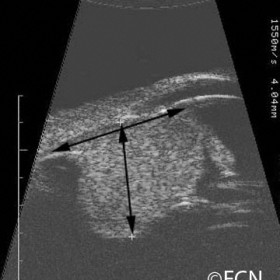

Ciliary Body Melanoma

Ciliary Body Melanoma- 20 MHz B-scan reveals a collar-button shaped ciliary body melanoma (this technique is used to measure tumor size).